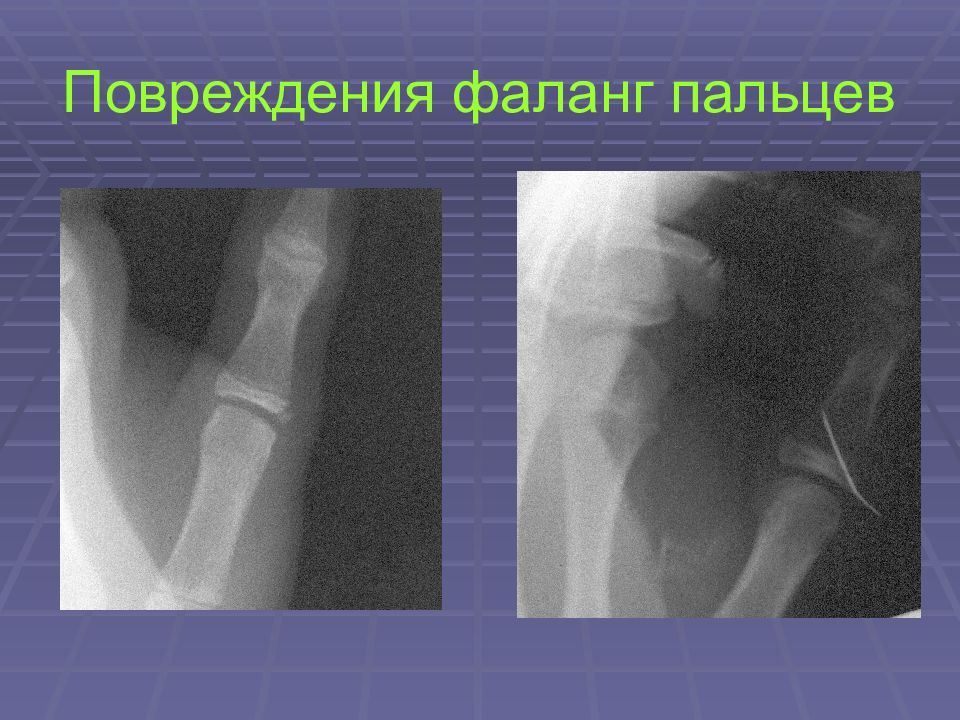

• Повреждения фаланг пальцев